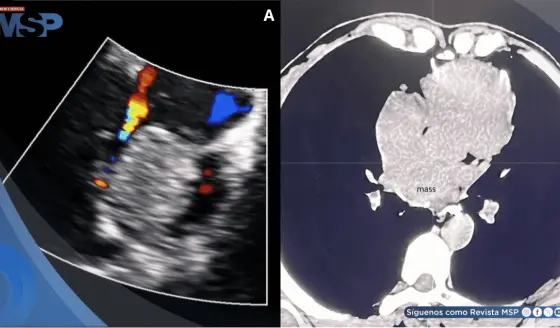

Figura 2: (a) TC preoperatoria con contraste que muestra una cavidad retroperitoneal izquierda que contiene intestino, bazo y un riñón funcional de tamaño normal, con un pedículo renal alargado. (b) Ecografía Doppler postoperatoria que muestra un flujo sanguíneo normal en la arteria renal y la vena renal. (c). TC postoperatoria con contraste que muestra el riñón con una excreción normal del contraste.